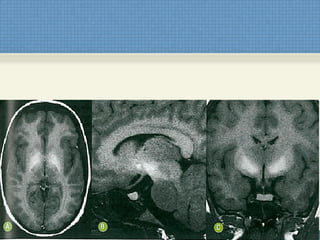

ACHADOS DE IMAGEM

RM de Crânio + Cervical + Torácica

• T1:

 Discreto espessamento da medula espinal sem

evidência de alteração de sinal ou impregnação

pelo contraste;

• T2:

– Hiperssinal linear contínuo e simétrico dos

funículos posteriores e laterais. Não é

necessário o achado combinado.

• Hiperssinal em T2/FLAIR da região bulbar posterior,

por extensão espinal no fascículo gracil e cuneiforme;

• Hiperssinal T2/FLAIR em substância branca

subcortical difuso e assimétrico;

Explica a depressão e déficit

cognitivo?